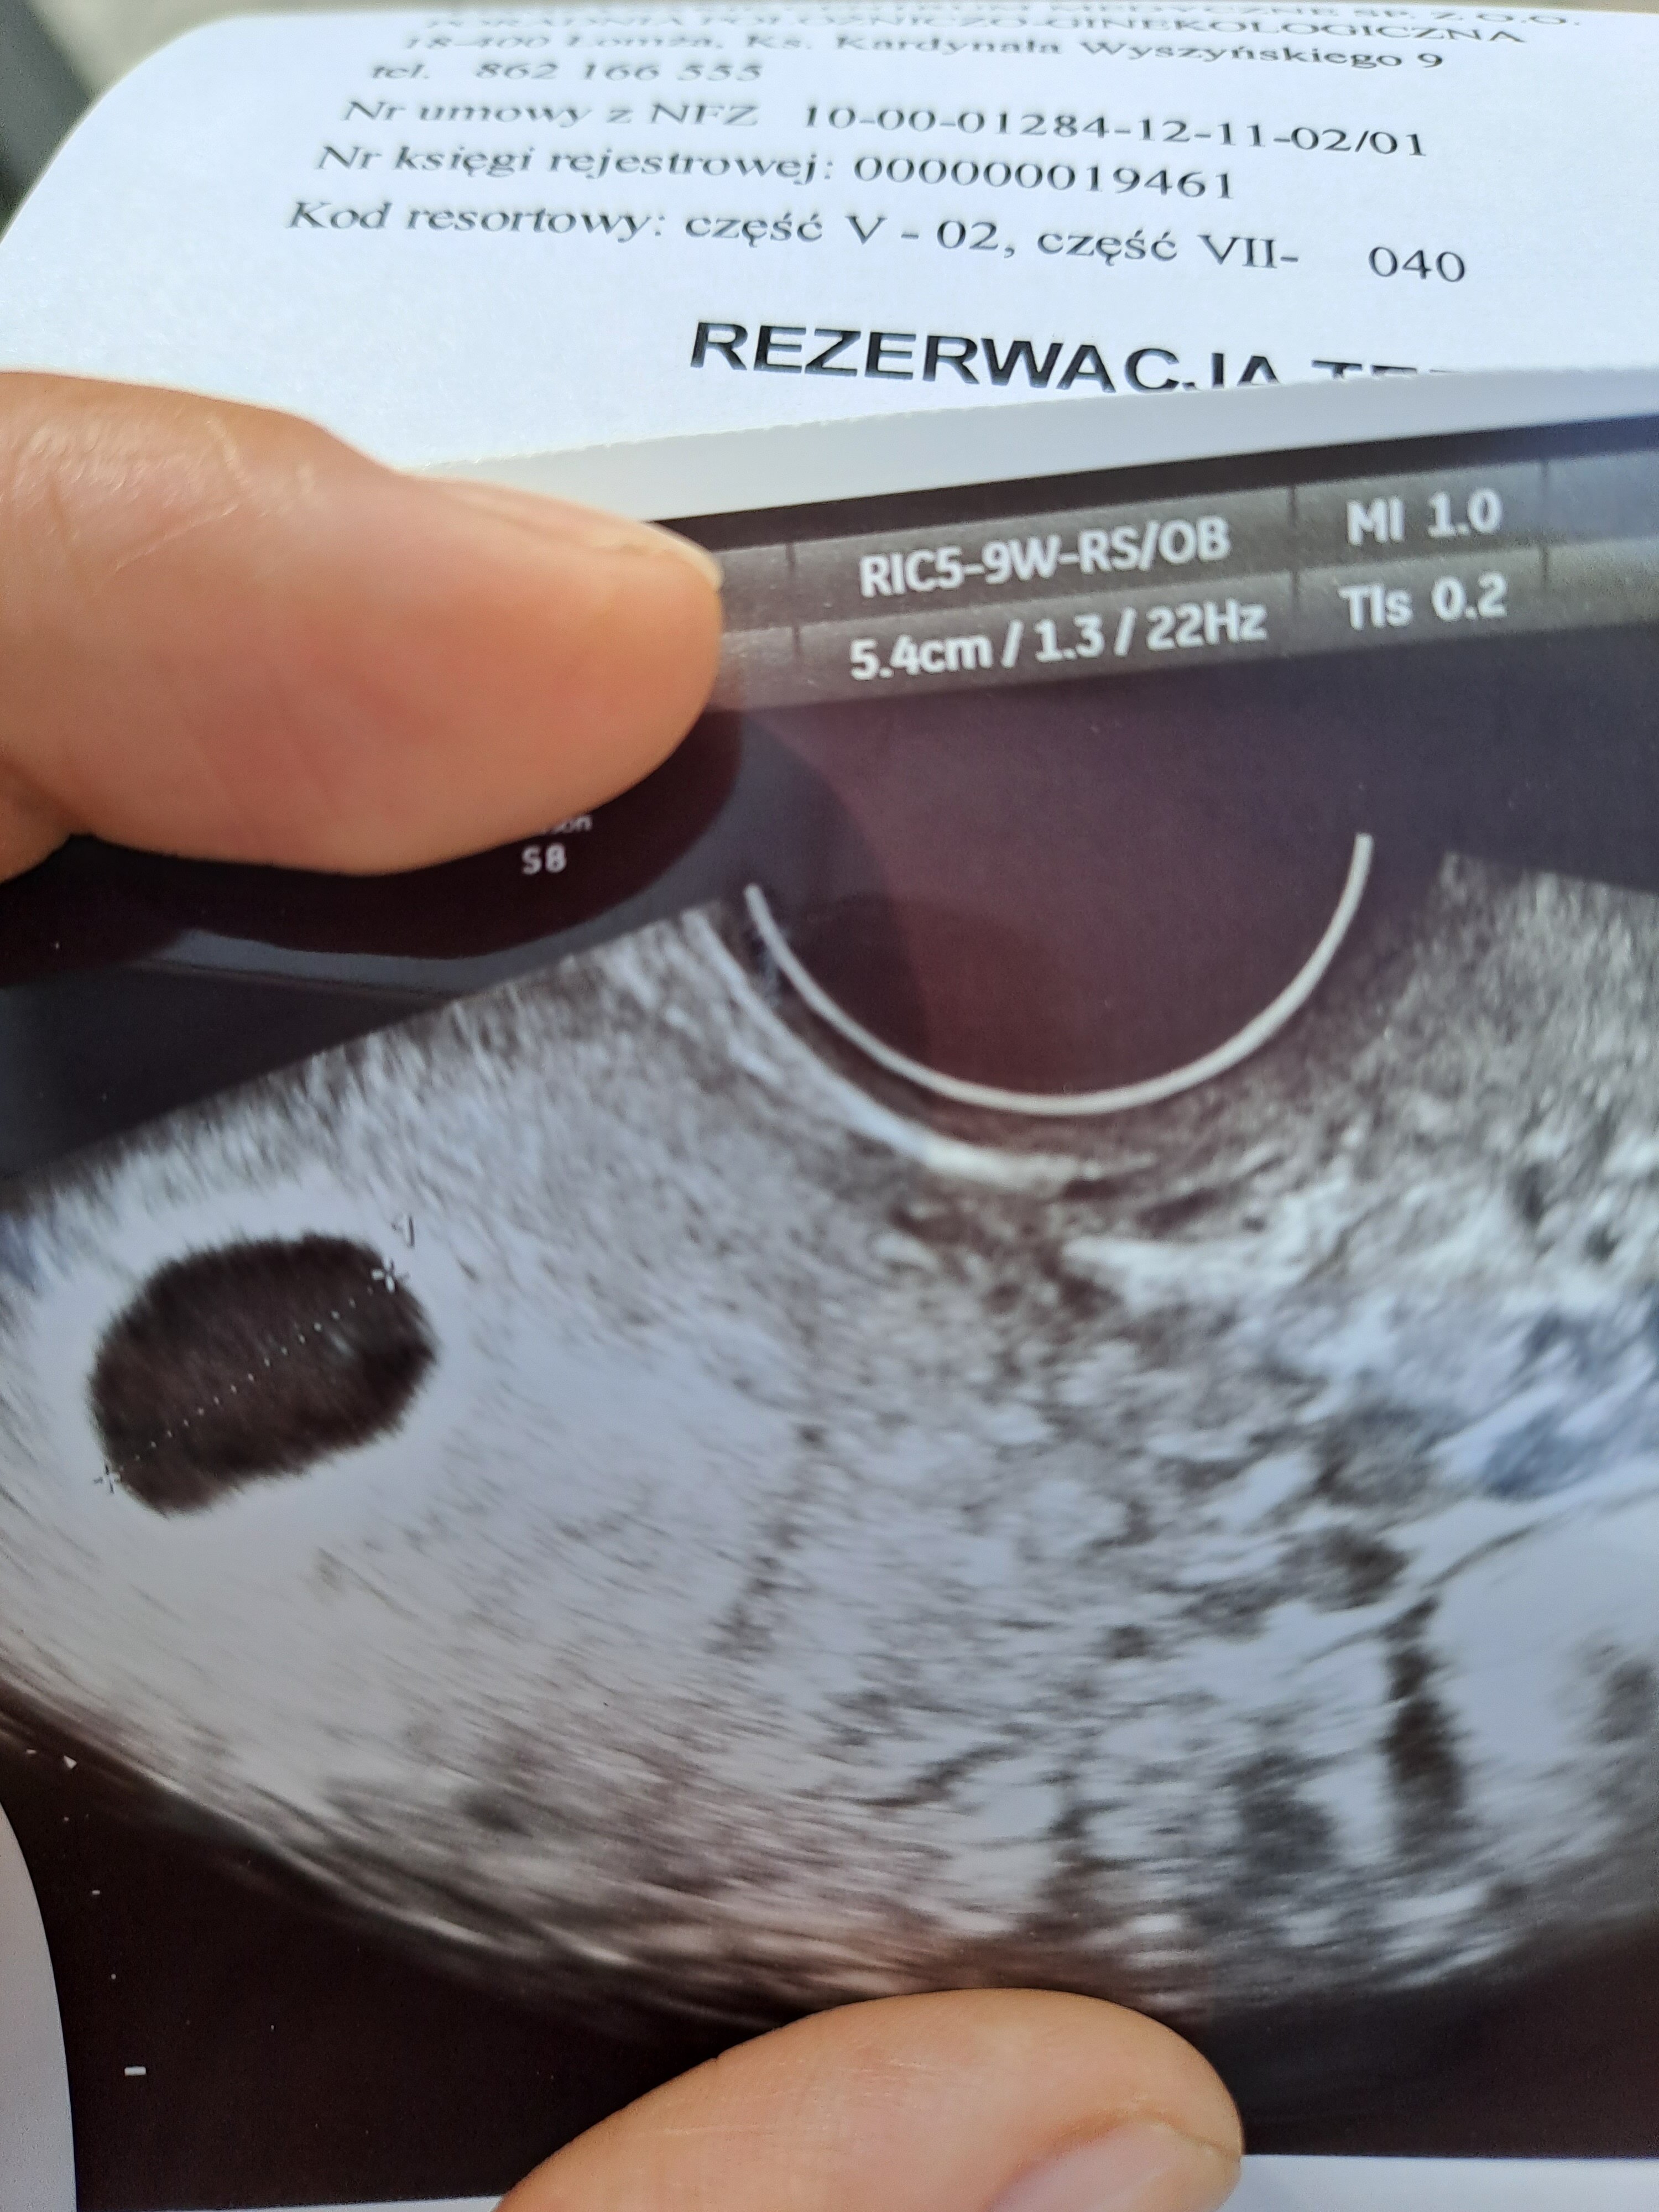

Ciąża bezzarodkowa

W pt byłam u lekarza, a ten stwierdził że moje jajo płodowe jest puste. Z z OM wynika że to 8tydz ciąży...Jajo ma prawie 15mm. 30.08 idę na kolejną wizytę. Jestem przerażona...proszę o kilka słów otuchy...wsparcia.

Właśnie lekarz nic mi nie powiedział o pęcherzyku. Mój cykl nie istniał samoistnie. Brałam lek clostilbegyt.

Mam jeszcze nadzieję, że ciąża jest młodsza....może lekarz miał złe usg. Jak tak się dopatruje to coś widzę na zdjęciu...może to już schiza.